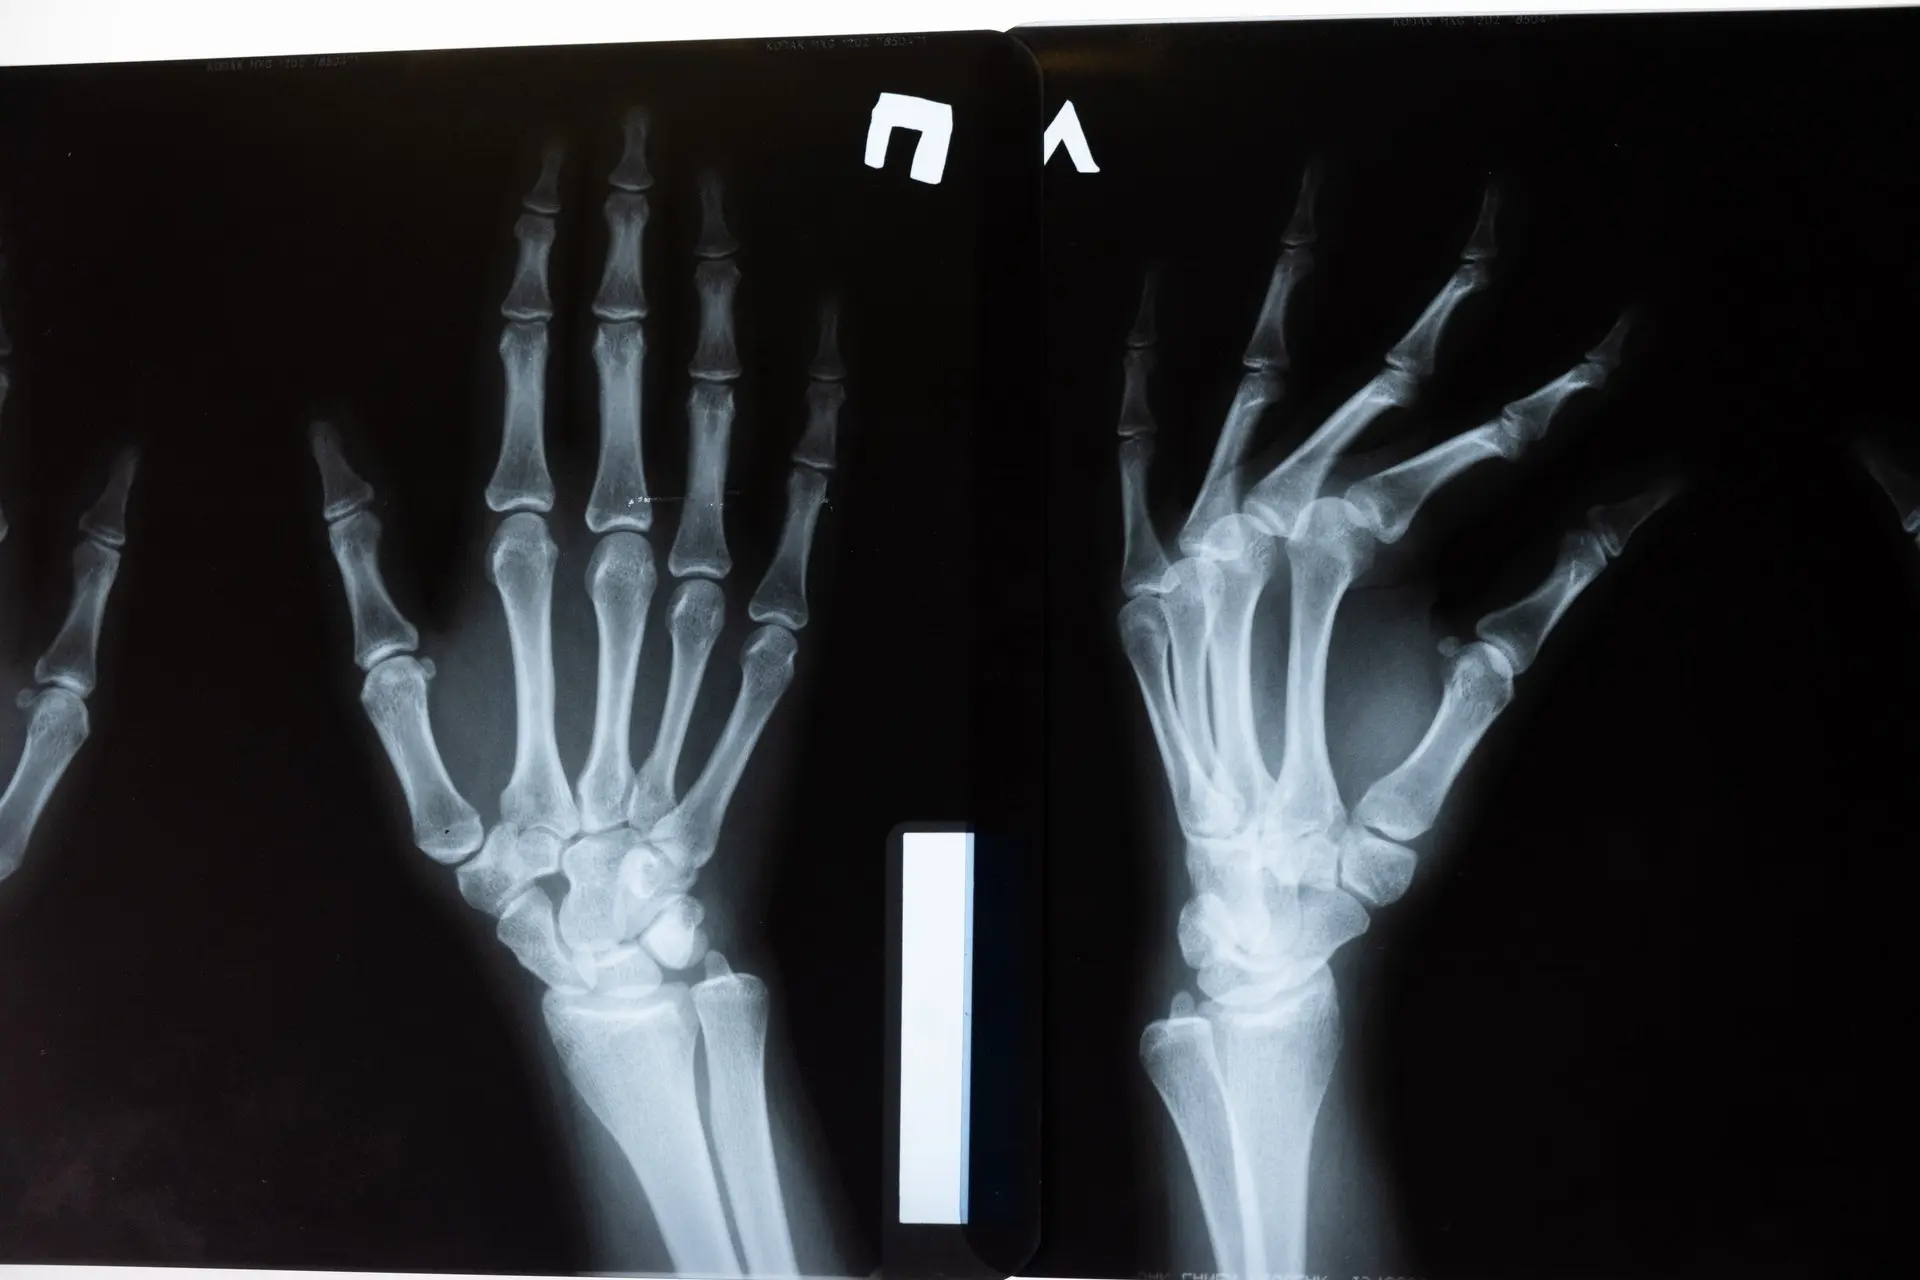

Guzki reumatoidalne, zwane także guzkami HeberdenaLink otwiera się w nowej karcie, pojawiają się w obrębie stawów palców u rąk. Występują pod skórą i można zaobserwować je na wyprostowanej powierzchni dłoni. Początkowo nie są zbyt widoczne, jednak z biegiem czasu przybierają bardzo nieestetyczny wygląd. Osoby dotknięte tym problemem – szacuje się, że w większości dotyka on kobiet w różnym wieku – skarżą się, że dłonie przypominają „szpony”, a ich kształt zaczyna utrudniać wykonywanie czynności manualnych.

Pojawienie się guzków reumatoidalnych na palcach wskazuje na to, że organizm cierpi na reumatoidalne zapalenie stawówLink otwiera się w nowej karcie (RZS). Nie jest to wczesny objaw tej dolegliwości, ale raczej jej konsekwencja. Dane wskazują, że guzki tego rodzaju to charakterystyczna przypadłość około 25% osób cierpiących na RZW, jednak są to zmiany świadczące o łagodnym przebiegu choroby.

Guzki reumatoidalne we wczesnym stadium rozwoju nie powodują bóluLink otwiera się w nowej karcie. Nie jest to jednak powód, aby zignorować tę dolegliwość. Do skutków uszkodzenia chrząstki stawowej rąk – a jest to przecież silnie związane z powstawaniem guzków – należą m.in.: obrzęk stawów, ich usztywnienie oraz znaczne ograniczenie sprawności ruchowej. Osoby cierpiące na tę przypadłość zwracają też uwagę na uciążliwy ból dłoni, który jest efektem ucisku guzków na nerwy. Wyraźne zgrubienie dłoni oraz „szponowatość” palców przeszkadza w wykonywaniu czynności manualnych, takich jak szycie, pisanie czy zapinanie guzików. Dolegliwość ta ma charakter przewlekły i bez wdrożenia odpowiedniego leczenia objawowego może doprowadzić do ciężkich deformacji, a nawet do kalectwa. Nie da się jej całkowicie wyeliminować – tak jak dolegliwości typu obrzęk nóg u starszej osoby – jednak odpowiednie środki złagodzą jej przebieg.